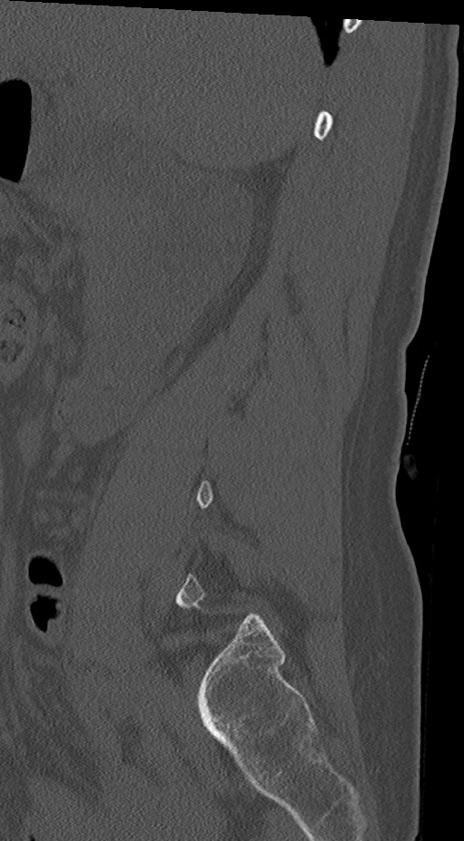

腰椎CT

冠状断像